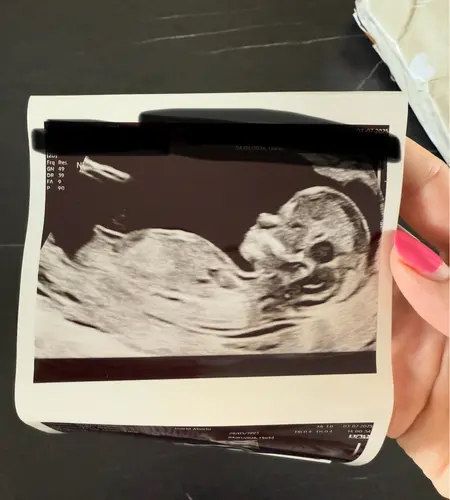

Wat denken jullie 馃┑馃┓

Wat denken jullie?

Iemand ??

Op basis van de skull een jongen 馃挋

Jongen denk, maar met deze theorie blijft het een grote gok. Nub is betrouwbaarder als je wat verder bent

Als ik de echo vergelijk met die van mijn zoontje zeg ik jongen 馃┑

Het lijkt wel op dit moment jongen maar is nog vroeg en kan veranderen

Wat denken jullie aan de hand van de Skull?馃挋馃┓